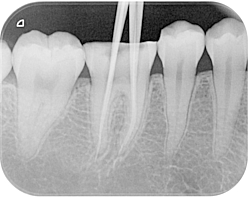

Digital Xrays

Using a small sensor placed briefly in the mouth, an x-ray image of high analysis is obtained.

This sensor functions as a miniature camera that is more sensitive to the radiation of the radiographic apparatus with respect to the normal light.